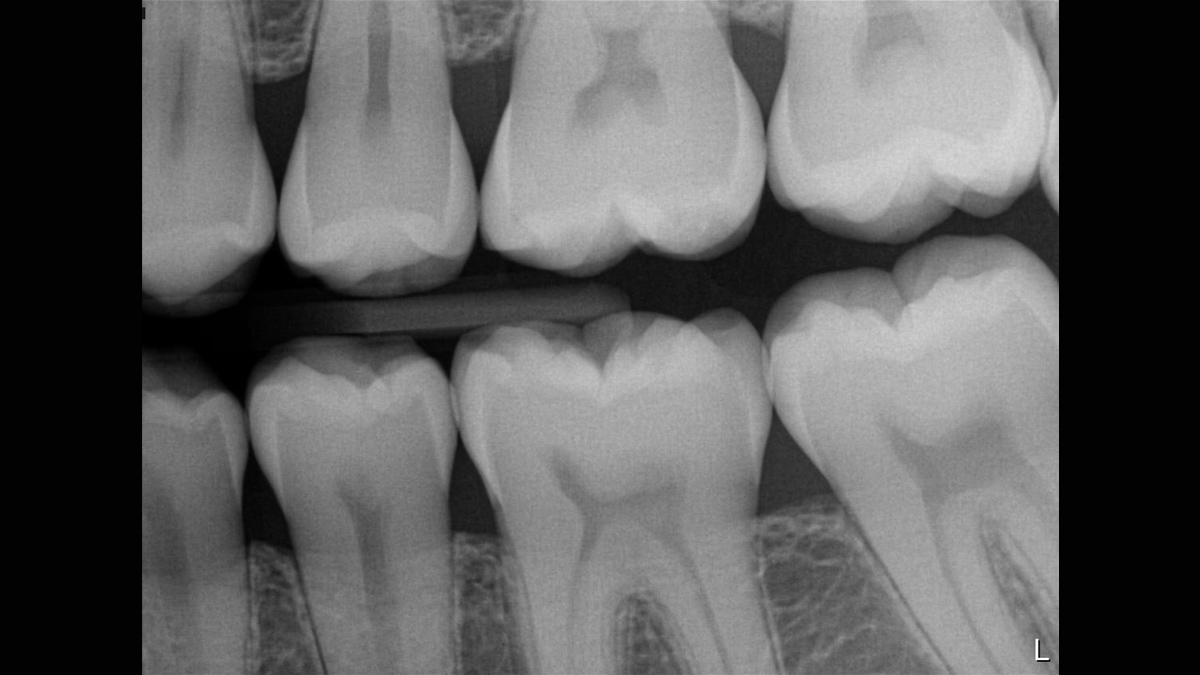

Xios XG Supreme proporciona una resolución teórica de 33 pl/mm y un tamaño de píxel de 15 μm que ofrece una excelente calidad de imagen sin el tiempo de espera adicional causado por un proceso de revelado o escaneo.

La excepcional calidad de las imágenes es solo el comienzo con los sensores intraorales Xios XG Supreme. El deslizador de nitidez dinámica le permite ajustar las configuraciones de su diagnóstico en términos de nitidez. Hay disponibles opciones adicionales del deslizador para modificaciones de brillo y contraste. Después de la configuración, las imágenes se muestran de manera eficiente para mejorar sus capacidades de diagnóstico, lo que le ahorra tiempo valioso. Un solo clic del mouse le permite obtener la imagen correcta para cada situación de tratamiento y mejor soporte clínico.

Los sensores Xios XG Supreme tienen cinco opciones diferentes de filtro: odontología general, endodoncia, periodoncia, restauración y caries. Estas vistas clínicamente específicas están diseñadas para optimizar su diagnóstico, mejorando la imagen para satisfacer sus necesidades.